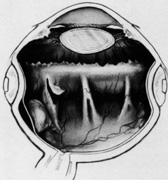

Fig. 40. Scleral perforation during suture placement with subretinal hemorrhage and retinal break.